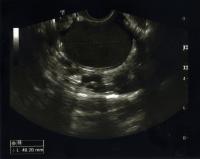

But we don’t always see all three of those things at the same time. Sometimes symptoms are subtle. Other times, people will have blood in their urine or stools or they will have painful bowel movements or pain with urination. Or they might have pelvic pain because they have an enlarged ovary from an endometrioma, a cyst that forms when endometrial tissue grows in the ovaries.

The gold standard is minimally invasive surgery with laparoscopy, an outpatient procedure where we put a camera into a small incision in the belly to examine the pelvic organs. We can take a clinical history and do a physical exam, which can raise the index of suspicion very high based on findings and what we hear from the patient, but we can’t confirm it definitively until we do the surgery. We look for the implants—the evidence of the endometriosis in the abdomen and pelvis. We also look at the ovary and whether any cysts are present. Depending on what we find, we will then assess the best treatment plan.